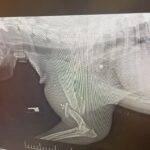

The people and pets below are Real. Please help us in supporting others, Directly. Without Judgement and without Applications.